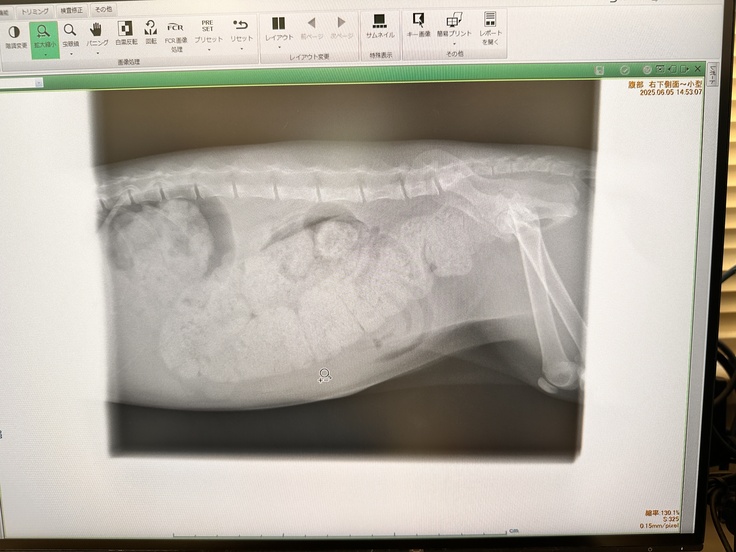

これがその時のレントゲンになります

お腹の中全部が💩なのが分かります

そして太くなってしまった腸管は元には戻らないとの事

膀胱は空っぽだけど、腸が便で埋まっている

との事でした